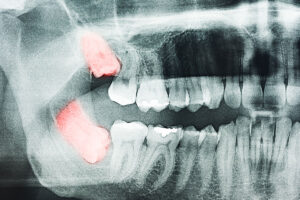

Affordable Wisdom Tooth Extractions in Brampton – Pricing & Options Explained Worried about the cost of removing a wisdom tooth? You’re not alone. Many patients delay wisdom tooth extraction due to uncertainty about pricing — but doing so can lead to worse problems down the road. At Polaris Dental in